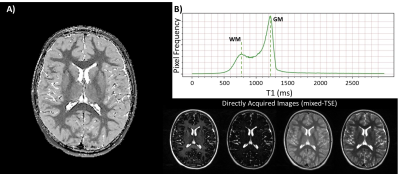

In vivo application of the qMRI-based T1 repolarization algorithm. A) Representative image of an extremely preterm born subject. Strong contrast can be seen between all tissue types, including white matter, grey matter, and cerebrospinal fluid. B) The repolarized T1 demonstrates a characteristic bimodal distribution, with clearly distinguishable peaks for white matter and grey matter. Directly acquired images from the mixed-TSE are shown for reference.